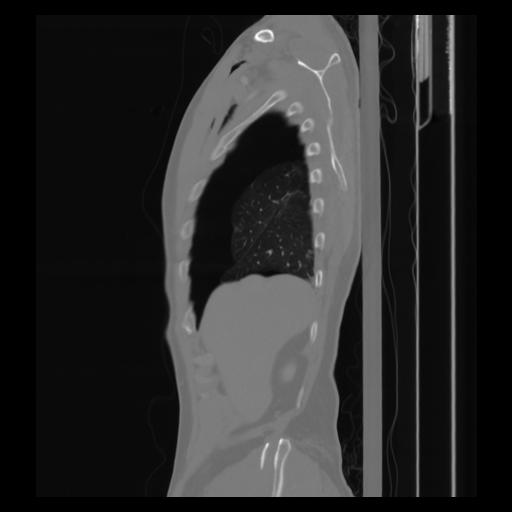

30 CUERPO,CE,Sagittal,3.000,CUERPO,Sagittal,